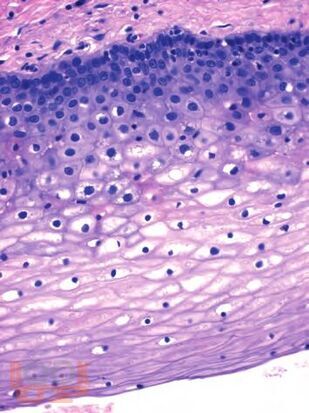

В практическом пособии рассматриваются основные принципы морфологического исследования при заболеваниях матки, гистофизиологические изменения шейки матки и эндометрия на протяжении менструального цикла и в разные возрастные периоды женщины, различные аспекты патогенеза и диагностические критерии доброкачественных и злокачественных поражений матки, значение иммуногистохимических исследований в интерпретации морфогенеза поражений и дифференциальной диагностики последних.

Особое внимание уделяется терминологии, приводится принятая в настоящее время гистологическая классификация опухолей шейки и тела матки (ВОЗ, 2014). Представлены также материалы, касающиеся состояния хориальной и плацентарной тканей при нормально протекающей и осложненной беременности, и современные сведения о гестационной трофобластической болезни.